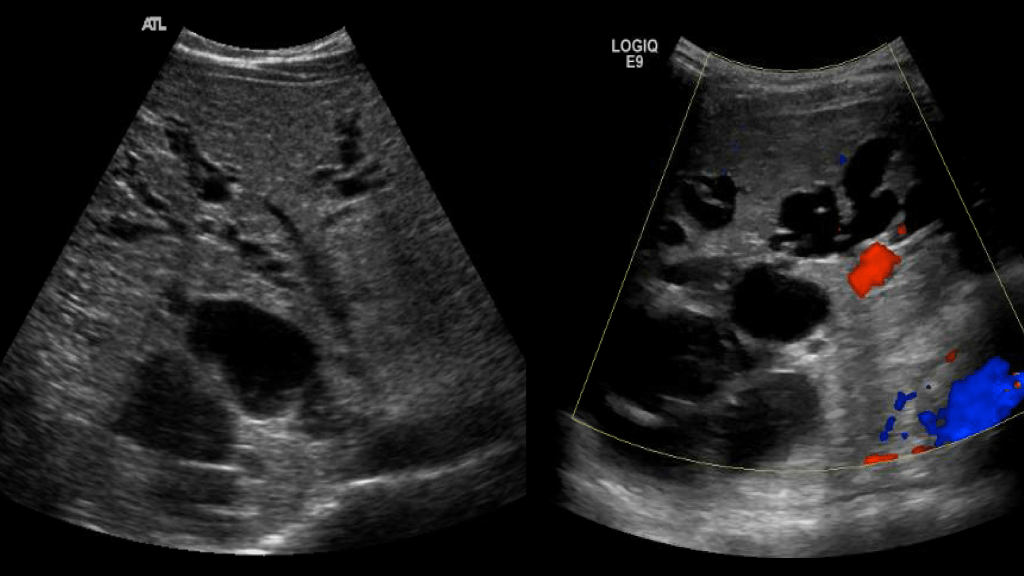

Caroli’s disease

Rare congenital disease of the intrahepatic biliary tree which leads to non obstructive saccular or fusiform (less common) dilatation of the intrahepatic bile ducts. There’s 2 types

Bile duct dilatation can lead to stasis of bile and sludge/stone formation. There is a predisposition to develop ascending cholangitis. It is common in patients with ARPKD and can be associated with hepatic fibrosis.